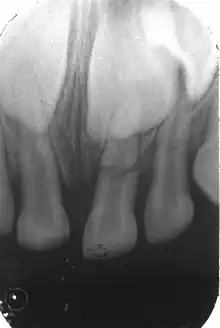

Fracture corono-radiculaire

Fracture corono-radiculaire : fracture de l'email, de la dentine, du cément avec ou sans atteinte pulpaire II y a une mobilité axiale et/ou latérale d'un fragment coronaire de la dent, avec une douleur à l'occlusion